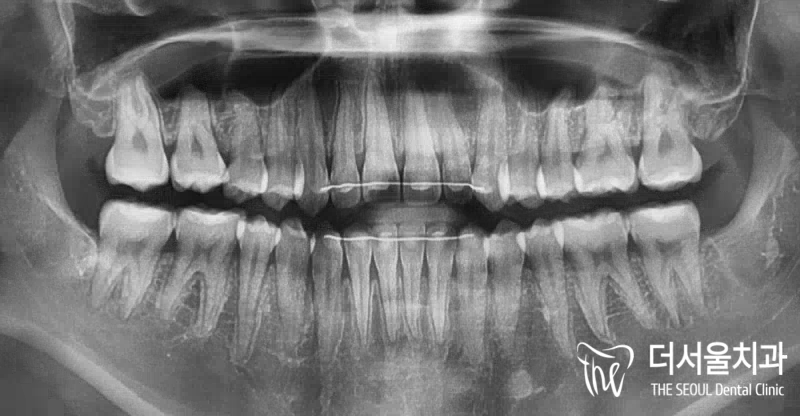

부정교합 2급 이라는 것은, 하악보다 상악이 더 전방에 위치되거나 또는 상악의 치아들이, 하악 치아들보다 더 앞쪽에 위치되어 있는것을 뜻하며

증세를 갖고 계셨던 분의 임상 증례를 보여드립니다. 교정 치료를 통해서 2급 부정교합이 개선 되었으며 치료를 끝으로, 턱 끝에 보형물